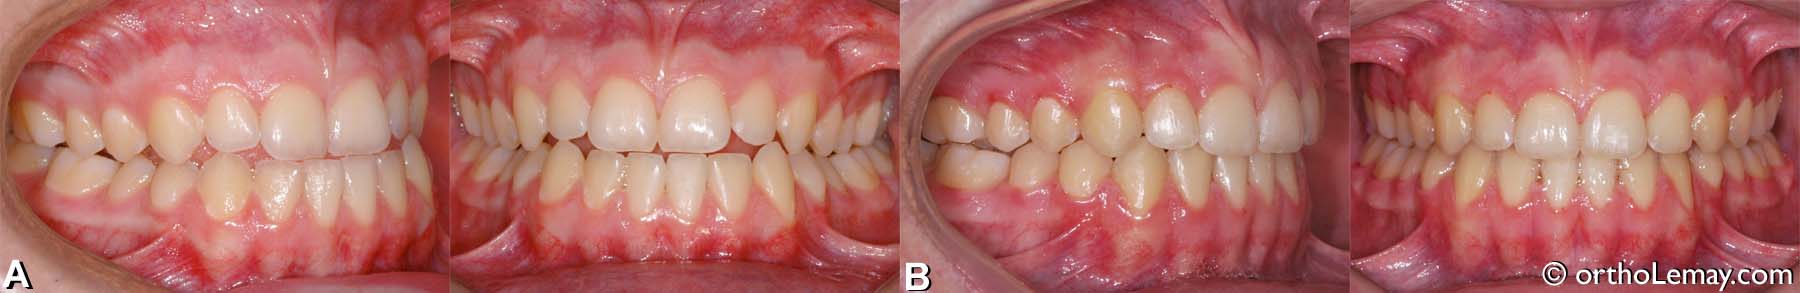

• Adolescent de 15 ans.

• (A) Malocclusion dentaire classe 3 (III) avec maxillaire étroit et important décalage sagittal du côté droit.

• (B) Après le traitement d’orthodontie.